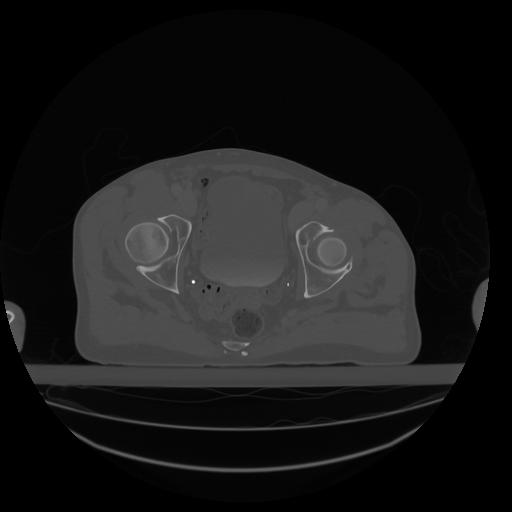

34 CUERPO,CE,Vol,1.0,CUERPO,,